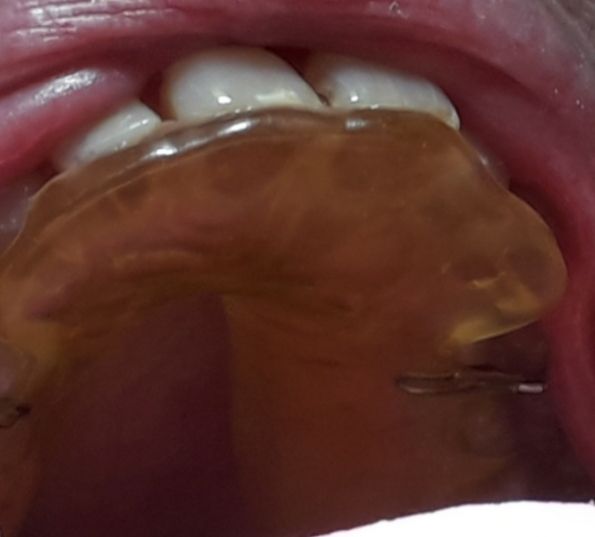

Foto e video